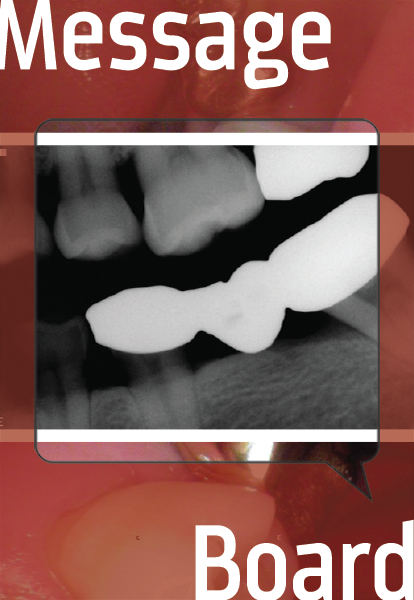

How to Do a Keyway Bridge

The keyway bridge is used to span an edentulous space while mitigating the stresses destructive to the natural dentition. This case and discussion show the technique and discuss variations.